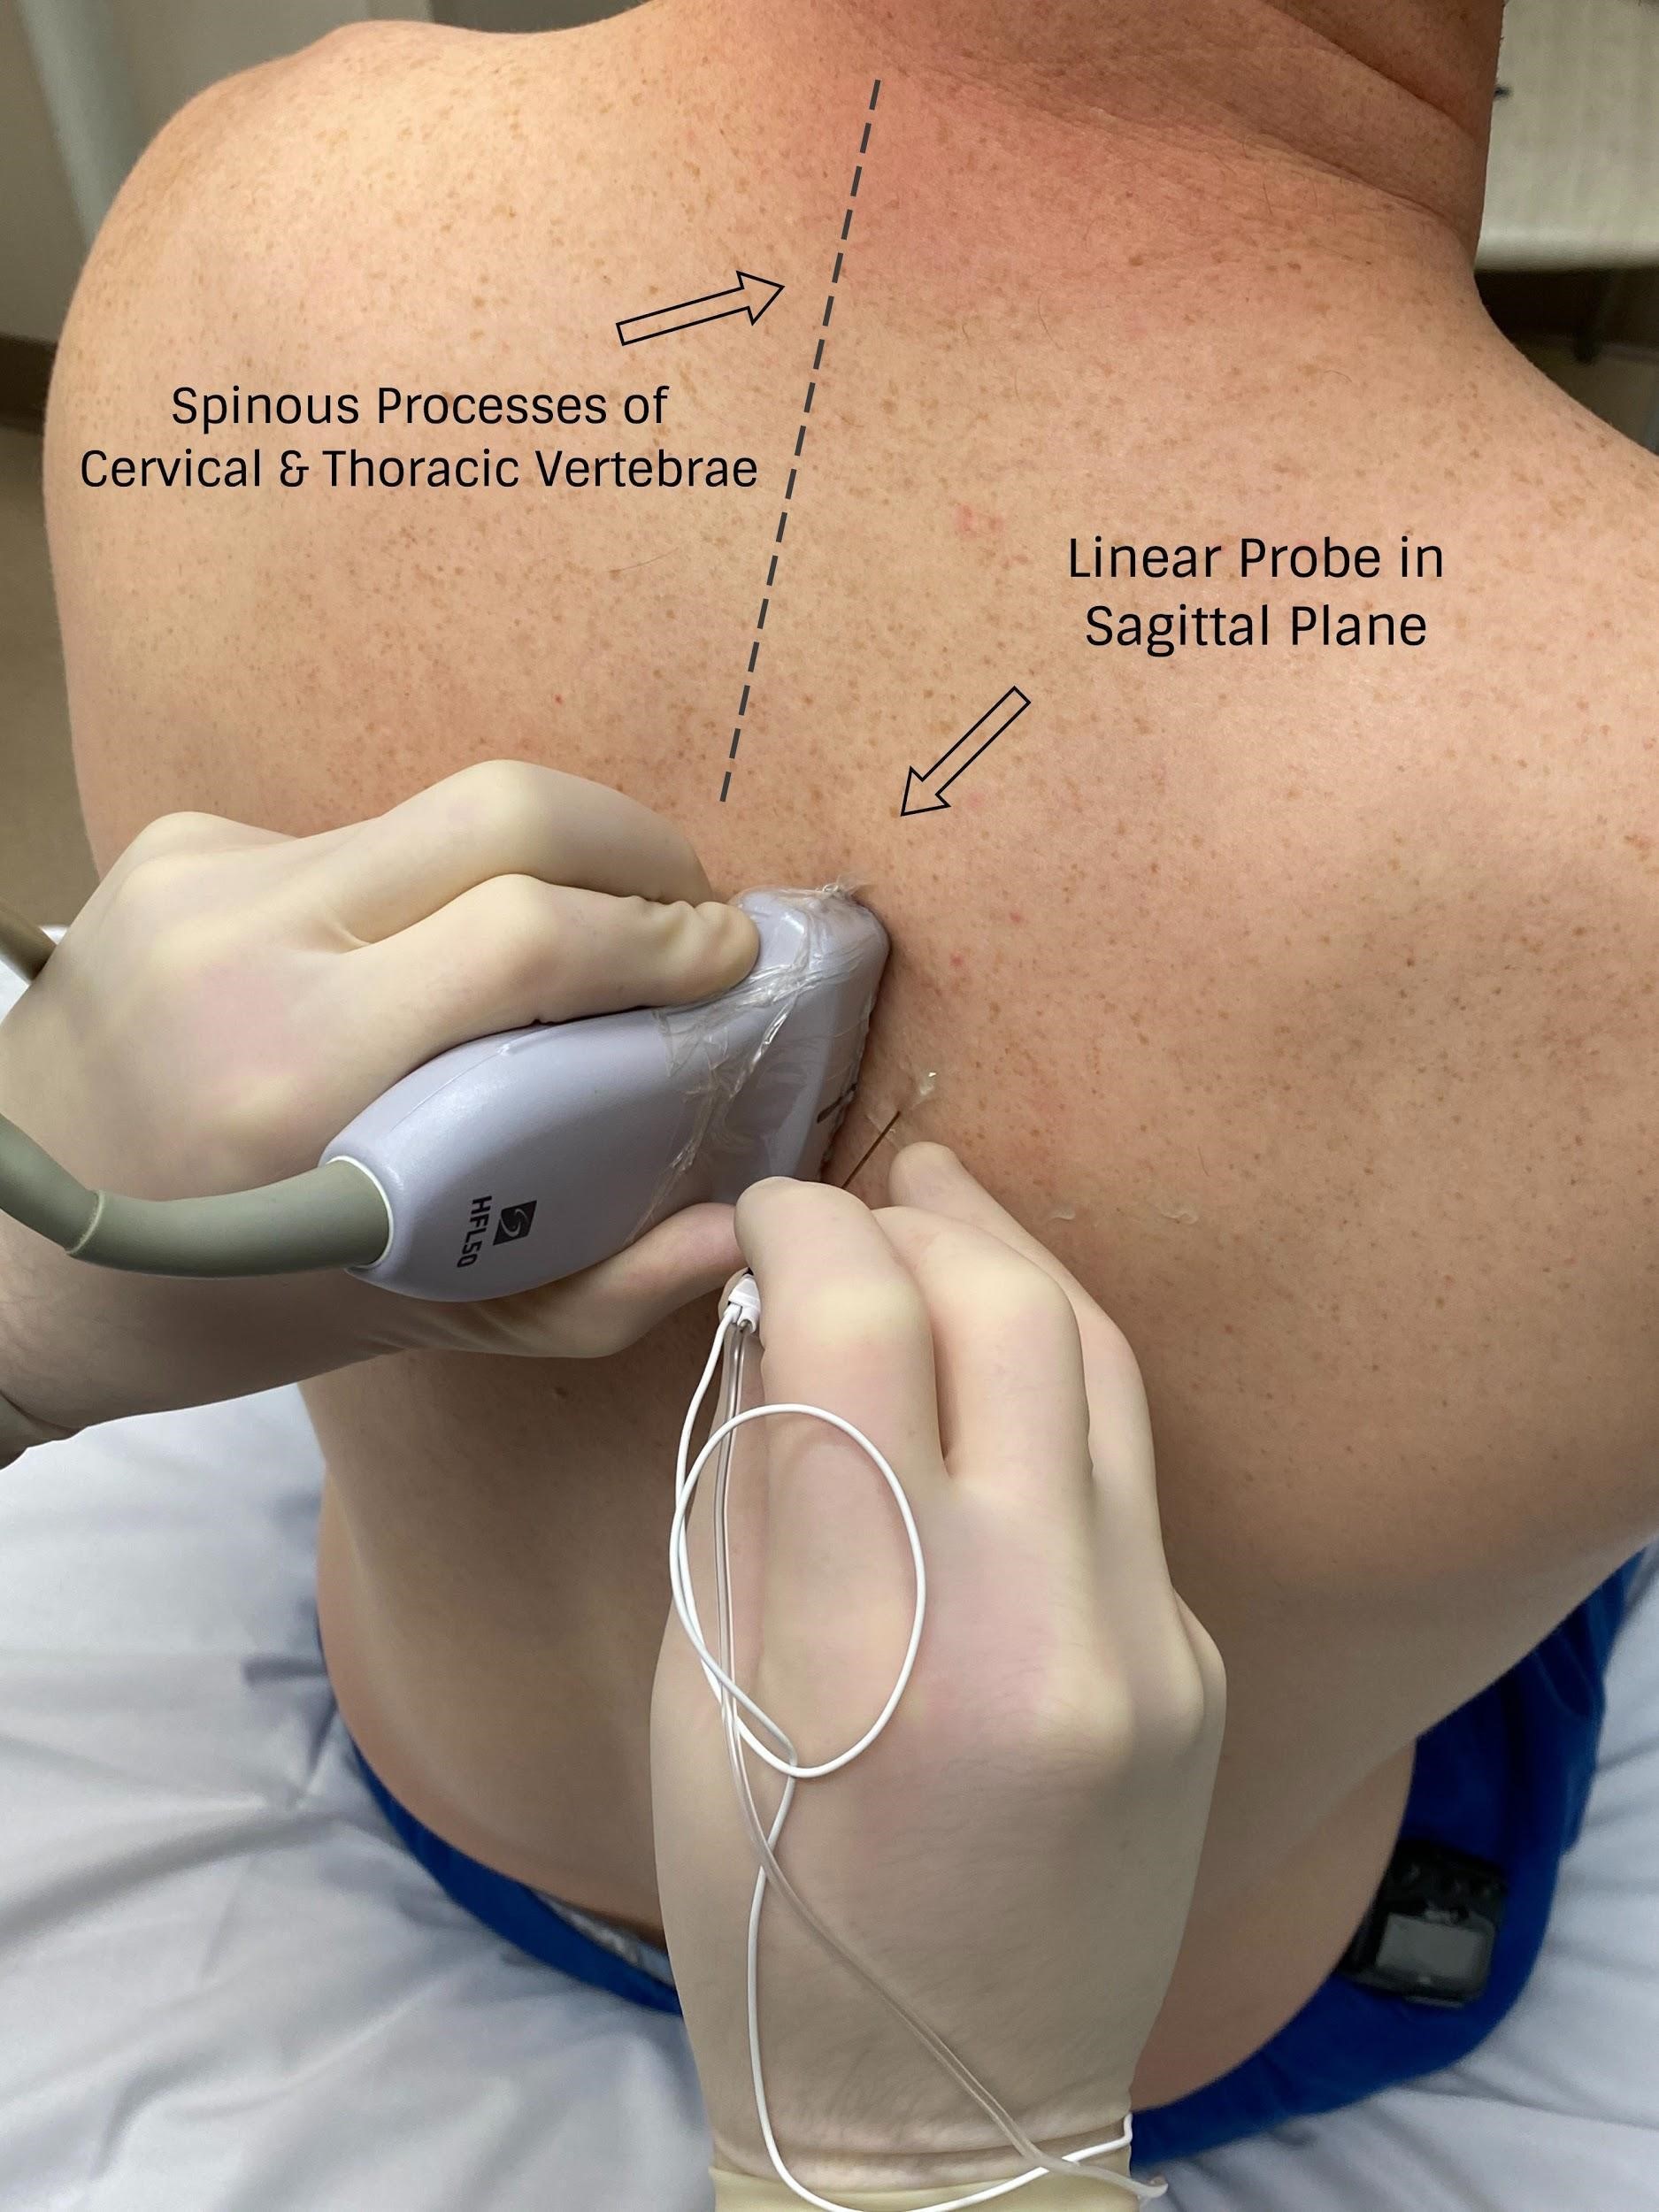

With PVB, deposit local anesthetic between the pleural and costotransverse ligament under ultrasound guidance using either an in-plane or out-of-plane needle approach. For the out-of-plane technique, hold the transducer (linear or curvilinear, depending on the patient’s body habitus) in the sagittal plane, allowing for a linear needle trajectory perpendicular to the skin (Figure 3). The pleura is visible in that plane between the ribs laterally and the transverse processes medially. In the transition from rib to transverse process, the bone image appears larger and squarer as the transducer is moved more medially (Figure 4). Hydrodissect with sterile saline to estimate the needle tip location when using an out-of-plane technique, with the downward/anterior bowing of pleura, or loss of reflection of saline upward/posterior, indicating injection into the paravertebral space. This is the preferred regional anesthetic technique at our institution and has provided effective surgical anesthesia for a variety of oncologic breast and thoracic procedures.

Figure 3: Probe position for out-of-plane paravertebral block

Image courtesy of Steven Ethier, DO.

In our clinical practice, a thoracic PVB is generally performed with ultrasound guidance with the probe oriented in the sagittal plane and the needle inserted out of plane relative to the probe. To provide surgical anesthesia, PVBs are generally performed at T2, T4, and T6. Essential equipment includes the ultrasound machine (linear probe of 10–13 MHz), local anesthetic, chlorhexidine or iodine prep solutions, block needle (typically 5 cm, rarely 10 cm), three-way stopcock, multiple sterile saline flushes, transparent dressing (or ultrasound probe cover for bilateral surgery), ultrasound gel, sterile gloves, additional faculty to assist with positioning and local anesthetic injection, and sedative and rescue medications.

With the patient seated, apply standard ASA monitors, administer supplemental oxygen, and initiate intravenous fluid administration. Sedation generally includes midazolam (2 mg) and/or fentanyl (50–100 mcg). Following sterile prep, position the ultrasound probe in the sagittal plane adjacent to the planned vertebral level approximately 3 cm off of the midline of the spine (Figure 3). Scanning from medial to lateral, first identify the transverse process and rib, taking note of their transition by change in shape and depth (Figure 4). Both structures will be seen in cross-section with pleura located anterior to the cephalad and caudad bony structures. Targeted injections should occur after the transition from rib to transverse process (the transverse process is located more medially and appears more squared-off in appearance).